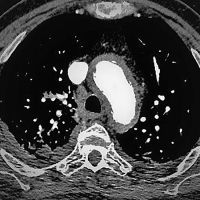

Thorax-CT

Abbildung 3: Thorax-CT mit Hyperdensität der Aortenwand und Verdacht auf ein intramurales Hämatom (IMH).

Aortenwand

Hyperdensität

IMH

intramurales Hämatom

Kardiologie